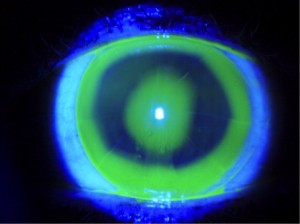

Entre los principales avances destacan las lentes esclerales, para usuarios con córneas irregulares –que no sostienen bien las lentes tradicionales– o para pacientes con ojo seco, a los que el uso de lentillas les irrita la córnea.

Ventajas: evitan el trauma mecánico ya que protegen la superficie, actúan como lentes terapéuticas al mejorar el ojo seco, y pueden retrasar la necesidad de transplante por queratocono” (adelgazamiento de la zona central de la córnea que produce astigmatismo irregular y que es la primera causa de trasplante corneal en pacientes jóvenes).

Inconveniente: Requieren un periodo de adaptación